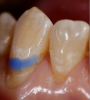

To best achieve an illusion of gingival tissues (ie, an admittedly imperfect simulation that is acceptable at a distance of 3 feet or more), it is imperative that the selected gingiva replacement composite demonstrate light-diffusing properties and a chameleon effect with surrounding natural tissues. The highly filled composition of the aforementioned Giomer-based composite contributes to light refraction and, therefore, optical properties similar to those exhibited by gingival tissues. The replacement composite should also provide a sufficient range of gingival color options to enable suitable shade approximation and custom matching (Figure 3 and Figure 4).

Fig 3. After using a very fine lead pencil to mark the curvilinear nature of the anatomical root area, a small spherical shaped amount of gingival colored composite material was placed on the tooth, light-cured, and used for shade determination with a custom shade tab.

Figure 3

Fig 4. Close-up view showing the pink composite shade estimation on the gingival tissue.

Figure 4